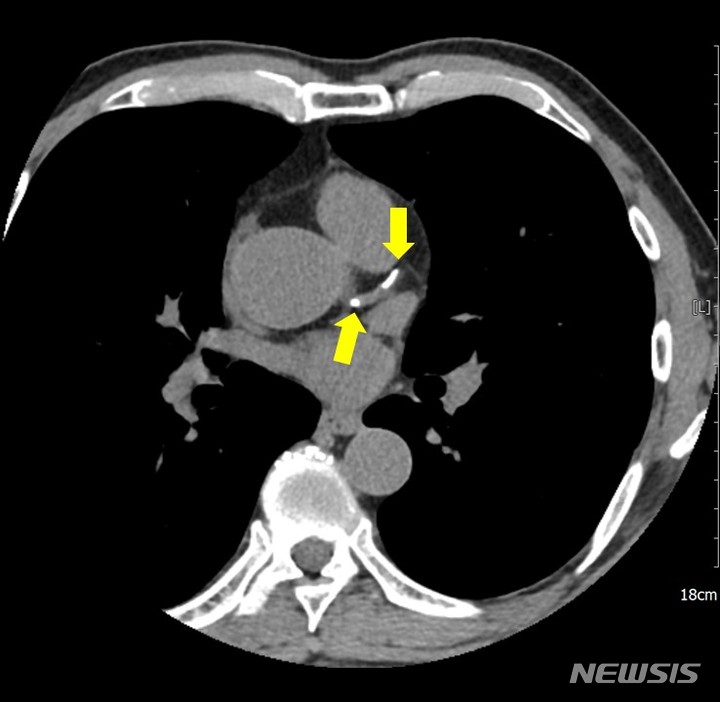

[서울=뉴시스]관상동맥 석회화란 심장에 산소와 영양분을 공급해주는 혈관인 관상동맥에 동맥경화증으로 칼슘이 쌓여 혈관이 딱딱하게 굳어지는 현상을 말한다. (이미지= 강북삼성병원 제공) 2023.03.08. [email protected].

[서울=뉴시스] 백영미 기자 = 45세 미만 젊은층의 관상동맥 석회화로 인한 심근경색·협심증 등 심혈관 질환 사망 위험도가 중·장년층보다 훨씬 높다는 연구 결과가 나왔다. 관상동맥 석회화란 심장에 산소와 영양분을 공급해주는 혈관인 관상동맥에 동맥경화증으로 칼슘이 쌓여 혈관이 딱딱하게 굳어지는 현상을 말한다.